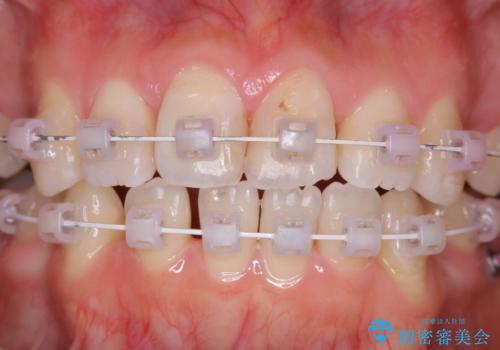

- ワイヤー矯正中のメンテナンスでPMTCを希望されました。染め出しを行い、歯ブラシ指導とPMTC30分コースを行いました。

この部分をしっかりと磨けるようになると、虫歯や歯周病を予防することができます。

矯正中にも、虫歯や歯周病予防をしっかり行うことが大切です。